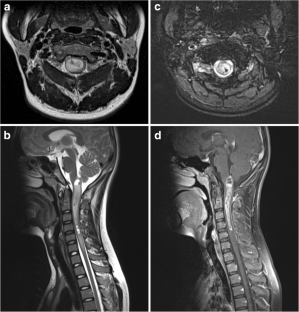

Diffuse midline glioma with histone H3 K27M mutation is a new entity described in the 2016 update of the World Health Organization Classification of Tumors of the Central Nervous System. The purpose of this study was to evaluate the clinical and imaging characteristics to predict the presence of H3 K27M mutation in spinal cord glioma using a machine learning–based classification model.

A total of 41 spinal cord glioma patients consisting of 24 H3 K27M mutants and 17 wild types were enrolled in this retrospective study. A total of 17 clinical and radiological features were evaluated. The random forest (RF) model was trained with the clinical and radiological features to predict the presence of H3 K27M mutation. The diagnostic ability of the RF model was evaluated using receiver operating characteristic (ROC) analysis. Area under the ROC curves (AUC) was calculated.

MR imaging features of spinal cord diffuse midline gliomas were heterogeneous. Hemorrhage was the only variable that was able to differentiate H3 K27M mutated tumors from wild-type tumors in univariate analysis (p = 0.033). RF classifier yielded 0.632 classification AUC (95% CI, 0.456–0.808), 63.4% accuracy, 45.8% sensitivity, and 88.2% specificity.

Our findings indicate that clinical and radiological features are associated with H3 K27M mutation status in spinal cord glioma.